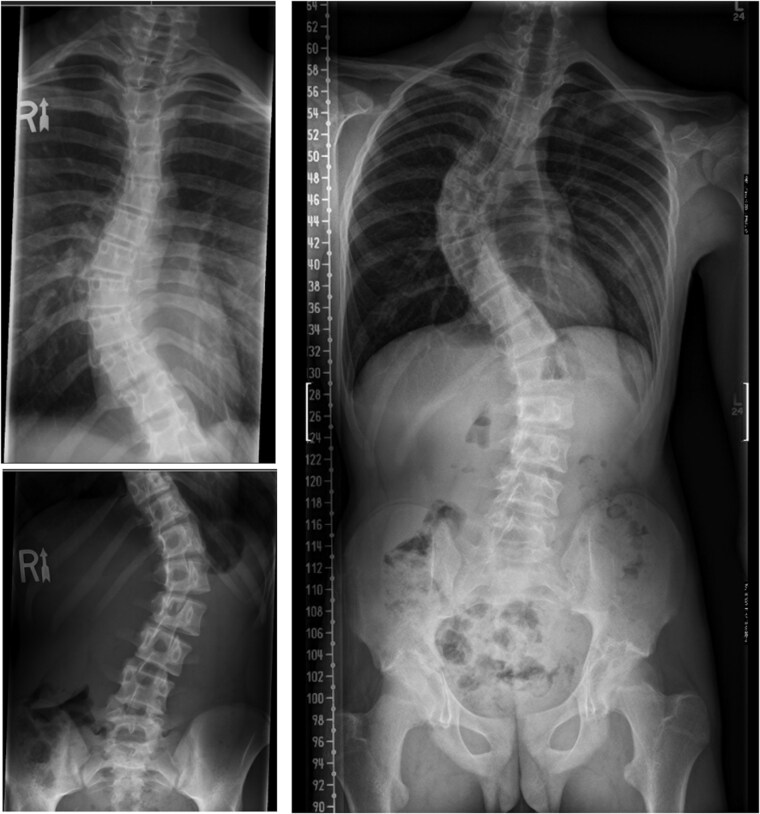

Objectives: Cobb angle is a standard method for quantification of scoliosis in adolescent idiopathic scoliosis to guide treatment decisions. Precise and timely curve detection can ensure early referrals, amenable for bracing. Radiology reports serve as a guiding tool for family physicians to expedite specialist referrals. Therefore, accurate and reliable measurement of Cobb angle at the community level is crucial. This retrospective study investigated the agreement in Cobb angle measurement between radiologists and spine surgeons.

Methods: Eighty radiographic reports (Cobb angle, Risser stage, and end vertebrae selection) completed by radiologists and spine surgeons were compared. To assess interrater reliability, interclass correlation coefficients (ICC) with 95% confidence intervals (CIs) were computed. ICC < 0.70, 0.70 to 0.79, 0.80 to 89, and 0.9 to 0.99 were considered poor, fair, good, and excellent reliability, respectively. All radiographs were assessed for quality.

Results: The agreement between spine surgeons and radiologists was poor (ICC = 0.65, 95% CI: 0.13 to 0.97). The agreement between spine surgeons and community radiologists was poor (ICC = 0.45, 95% CI: 0.17 to 0.66). Risser stage was not reported in 56 of the 80 reports. ICC between spine surgeons and radiologists for the Risser stage was poor (ICC = 0.625, 95% CI: 0.325 to 0.794). For end vertebrae identification, there was absolute agreement of end vertebrae identification in 23 of the 80 scans.

Conclusions: This study demonstrated a significant disagreement in scoliosis measurement between radiologists and spine surgeons, which significantly impacts appropriateness of referrals. Methods to improve triaging using allied health professional (i.e., nurse practitioners) may help ensure that patients presenting with scoliosis are referred in a timely manner.